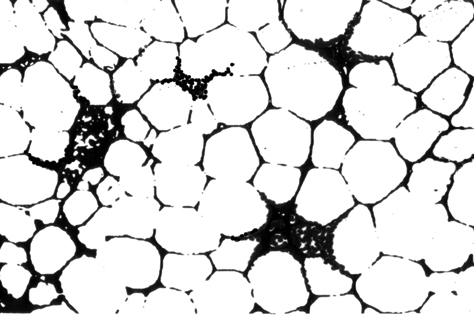

細胞存在パターン;左:hypo-diffuse 右:hypo-patchy

Hypo-diffuseは存在すれば「病気」の異常な状態とみなしてよい。Hypo-patchyは高齢者骨髄に似る所見